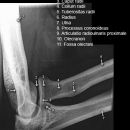

Ellenbogen seitlich (2. Ebene radio-ulnar)

Beurteilungskriterien

- Weichteilzeichen: Verlagerung des ventralen (proximal der Fossa coronoidea bis 5mm breit ist normal) und dorsalen distalen Humerusfettkörpers (normalerweise nicht sichtbar), Supinatorfettlinie: normalerweise etwa 3-4cm lang und 2-3mm breit, parallel zum proximalen Radius

- Target areas: vordere und hintere Humeruskontur, Radiusköpfchen, Processus coronoideus (evtl. zusätzlich 45°-Schrägaufnahme), Olecranon, harmonische Darstellung des Radiusköpfchen? Impressionen? Stufe? Verdichtungen, Fissur? Knickbildung?

- Auftreten, Verschmelzung und Lokalisation der Epiphysenkerne -> Verlagerung? vgl. Anatomie Kids! Viele kindliche Verletzungen sind anhand der Verlagerung der Knochenkerne differenzierbar! Evtl. Vergleich mit Gegenseite oder MRT hilfreich.

- Täuschungsmöglichkeiten: Persistierende Apophysen an Olecranonspitze oder Processus coronoideus, Kortikaliseinkerbungen als Residuen der Epiphysenfugen (v.a. des Olecranons)

- Kids: Kreuzung vordere Humeruslinie mit Radiushalsachse im mittleren Capitulumdrittel? Abweichung -> dislozierte, supracondyläre Humerusfraktur? Epiphysenfugenverletzung? Dislokation des proximalen Radius? Luxation?

Cave:

- 50% der Radiusköpfchenfraktur sind nicht disloziert und u.U. nicht nachweisbar -> bei klinischem Verdacht ist ein positives Fettpolsterzeichen nahezu beweisend! Greenspan-Aufnahme, evtl. CT oder MRT!

- Distale Humerusfraktur (Trochlea oder Capitulum) mit frontaler Bruchebene -> "Halbmondzeichen" durch plankonvexe(s) und in die Fossa cubiti dislozierte(s) Fragment(e) -> CT zur Beurteilung der Gelenkflächenverhältnisse.

- Komplexe Frakturen, Gelenkflächenverhältnisse? -> CT